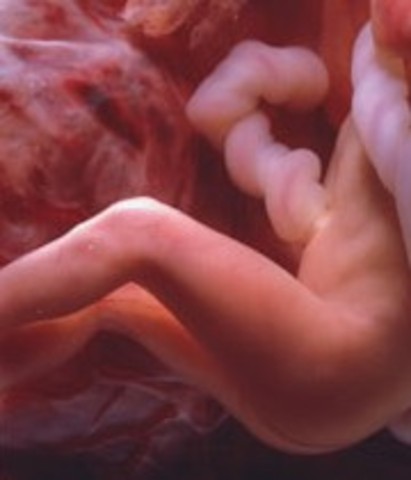

• week7

week7

1.Arm and leg buds begin to grow.

2.The heart is beating with one chamber

3.A dividing wall is formed in the heart

4.The baby's eyes and inner ears are starting to develop

5.the brain is growing

• week8

week8

1.Starts to practice moving (not felt by mom till week 20)

2.The face is beginning to take shape

3.first prenatal visit